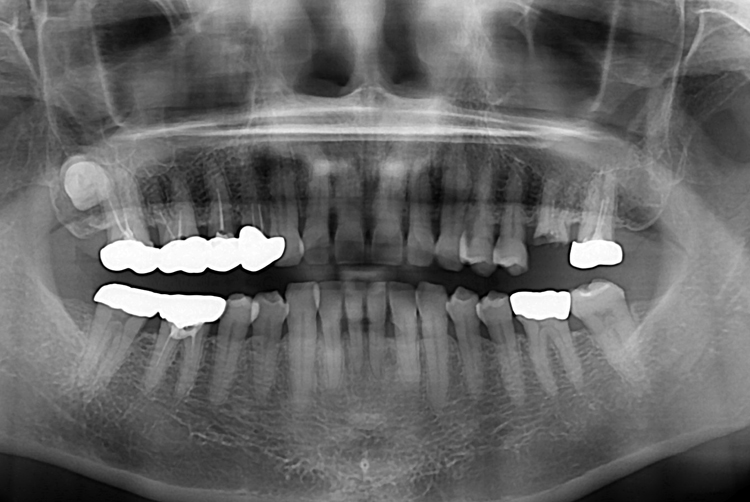

[임플란트] 어금니 임플란트

치료후 : 2017-10-31

세종치과는 많은 환자와 다양한 케이스를 바탕으로

항상 편안한 임플란트 수술을 제공하고자 노력하고,

오래동안 튼튼히 쓸 수 있는 임플란트 수술을 가장 큰 목표로 삼고 있습니다.